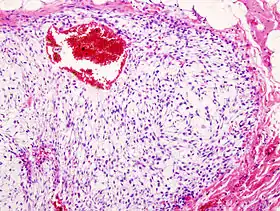

- Мікроскопічно. Хондроїдний матрикс, в якому розташовані хрящові клітини різного ступеня диференціювання і атипії, мітози не численні (деякі атипові), двоядерні і багатоядерні клітини, міксоматозні зміни. Хондроцити шикуються пучками або групами, ядра дещо збільшені, іноді химерної форми. Матрикс варіює від зрілого гіалінового хряща до міксоіднаї строми. Мітози не визначаються в хондросаркомі I, виявляються в хондросаркомі II і численні в хондросаркомі III ступеня злоякісності. У краях пухлина вростає в костномозковий простір, поширюючись між кістковими трабекулами, при руйнуванні кортикальної пластинки відбувається проростання пухлини в прилеглі м'які тканини.